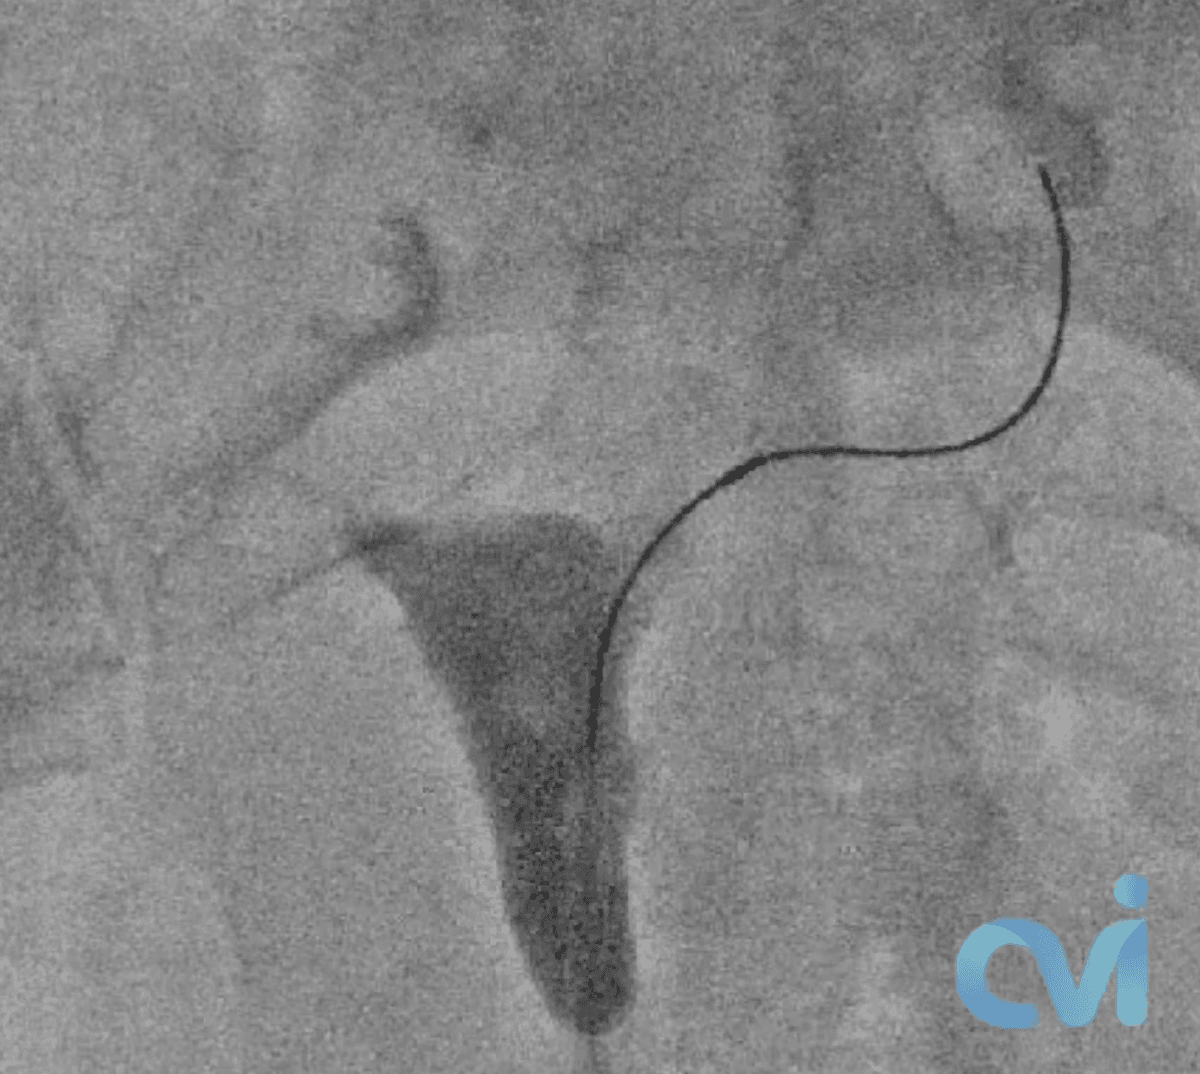

During the procedure, similar to a pelvic exam at your OBGYN, you lay on your back and a speculum is placed into the vagina. Then a small catheter is inserted through the cervix and a contrast agent, or dye, is injected into the uterus so an X-ray image of the uterine cavity can be obtained. When a fallopian tube blockage is identified, another smaller catheter and wire are threaded into the fallopian tube to open the blockage.